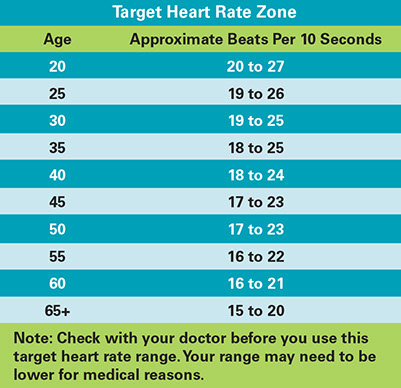

Target Heart Rate

This is 60-80% of your maximum heart rate. If you reach your target heart rate during the

aerobic part of your workout, your pace is good.*

To find out if you reach your target heart rate, check your pulse. Check it 10 minutes after you start your workout.

* Place your fingers (not your thumbs) on one side of your neck below your jawbone. Or, check it on the inside of your wrist.

* Count the number of tiny beats you feel in 10 seconds.

* Find the line with your age (or the closest one to it) in the “Target Heart Rate Zone” box.

* Is the number of beats you counted in 10 seconds in the range of numbers on the line next to your age? If so, you have reached your target heart rate.